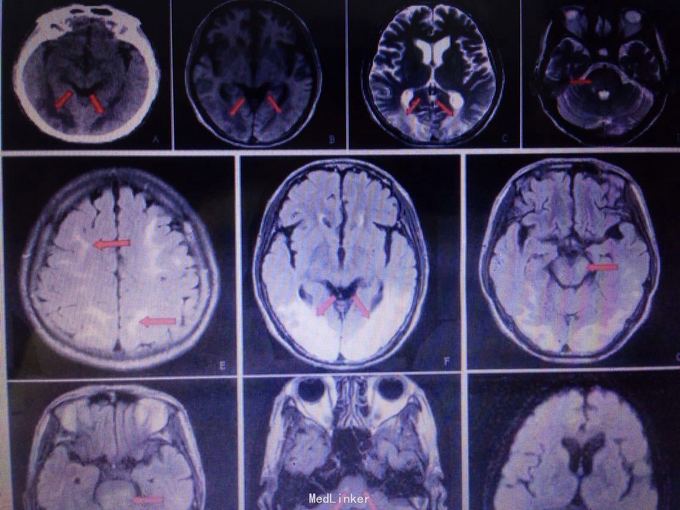

查体可见血压升高,昏睡,双眼视力眼前光感,眼球水平运动受限,视物重影,肌力约3-4级。 头颅CT见双侧枕叶皮层下对称低密度灶。 MR提示双侧枕叶下长T1对称病灶,flair相为高信号。腰穿脑脊液未见明显异常。

患者经治疗意识状态逐渐恢复,复查颅脑MR提示原有病灶较前明显减少。考虑患者可逆性后部脑病综合征诊断较为明确。